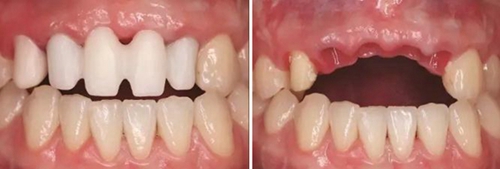

(5)2016年1月:軟組織塑形10個(gè)月后,牙齦形態(tài)穩(wěn)定,制取終印模行個(gè)性化全瓷修復(fù)。

①制取個(gè)性化印模帽:首先將臨時(shí)修復(fù)橋體取下后,酒精棉球擦拭干凈,連接相應(yīng)替代體,將該裝置整體插入流動(dòng)性較好的硅橡膠中,待其完全固化后,將臨時(shí)修復(fù)橋體擰松并取下,將硅橡膠內(nèi)的替代體連接開窗轉(zhuǎn)移桿,在硅橡膠制取的穿齦輪廓與轉(zhuǎn)移桿之間用Pattern Resin成型樹脂(GC公司,日本)充填,待成型樹脂凝固后取下進(jìn)行修整拋光,用于最終連于口內(nèi)后制取印模。

②制取開窗印模:13行纖維樁修復(fù)后牙體預(yù)備,排齦后采用DMG Light+Heavy加聚型硅橡膠(DMG,德國(guó))制取開窗式印模,比色,檢查印模制取情況,確認(rèn)準(zhǔn)確無(wú)誤后,連接替代體,涂布分離劑,注入人工牙齦材料,灌注超硬石膏。修復(fù)工藝中心運(yùn)用CAD/CAM計(jì)算機(jī)輔助技術(shù)進(jìn)行設(shè)計(jì),制作個(gè)性化的氧化鋯基臺(tái)以及氧化鋯全瓷修復(fù)體(Wieland威蘭德公司,德國(guó))。

③患者試戴個(gè)性化氧化鋯基臺(tái),檢查基臺(tái)就位情況,咬合狀況,基臺(tái)邊緣位于齦緣下<1mm,試戴氧化鋯基底,確認(rèn)基底就位良好,邊緣密合,完成永久修復(fù)體的制作??趦?nèi)戴入氧化鋯基臺(tái)后,扭矩扳手加力至30N后,聚四氟乙烯封閉螺絲通道,樹脂封孔。試戴全瓷修復(fù)橋體,檢查冠邊緣與基臺(tái)邊緣緊密接觸,與周圍軟硬組織相協(xié)調(diào),確認(rèn)鄰接以及修復(fù)體顏色良好。調(diào)整咬合,靜態(tài)咬合:正中咬合時(shí)后牙區(qū)均勻接觸,輕咬合時(shí)前牙區(qū)無(wú)接觸,重咬合時(shí)輕接觸,無(wú)牙合干擾或早接觸;動(dòng)態(tài)咬合:側(cè)方運(yùn)動(dòng)時(shí)尖牙引導(dǎo)或前牙組牙功能的交錯(cuò)保護(hù)牙合,前伸運(yùn)動(dòng)是切牙引導(dǎo)牙合,工作側(cè)和非工作側(cè)無(wú)牙合干擾。咬合調(diào)整完畢后高度拋光,口外用硅橡膠制備預(yù)粘接代型,超聲振蕩修復(fù)體,消毒后使用自粘接樹脂水門汀于口外預(yù)粘接并戴入口內(nèi),使用牙線去除多余粘接劑。拍攝X線片,確認(rèn)基臺(tái)和牙冠完全就位。

圖29 根管治療后的13行纖維樁修復(fù) 圖30 個(gè)性化轉(zhuǎn)移桿開窗取模

圖31 Index引導(dǎo)下試戴個(gè)性化氧化鋯基臺(tái) 圖32 個(gè)性化氧化鋯基臺(tái)于口內(nèi)就位

圖33 氧化鋯基底于口內(nèi)就位咬合正面觀 圖34 袖口正面觀

圖35 預(yù)粘接 圖36 戴入全瓷修復(fù)體正面觀

圖37 戴入全瓷修復(fù)體局部舌側(cè)觀 圖38 永久修復(fù)后微笑

圖39 永久修復(fù)后大笑